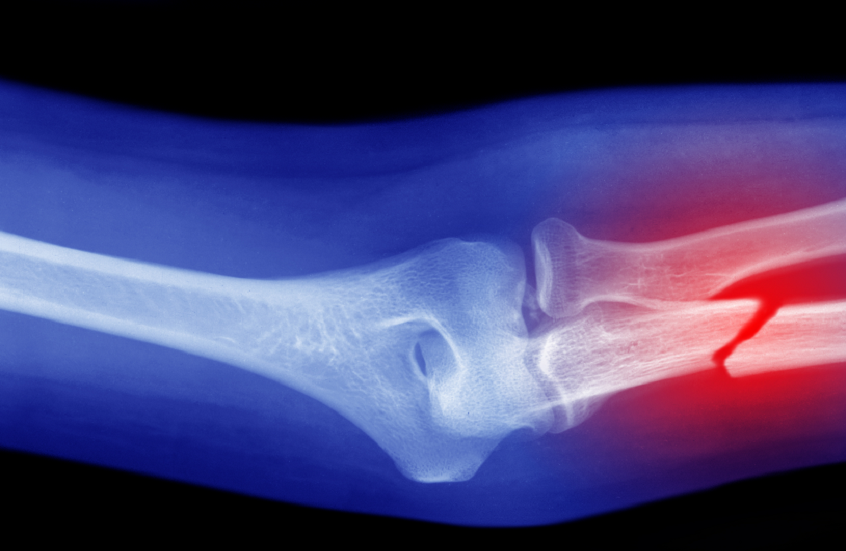

أظهرت دراسة أجراها علماء من جامعة تشيستر البريطانية أن اتباع حمية البحر الأبيض المتوسط قد يقلل من خطر التعرض لكسور العظام.

وأظهرت النتائج أن كثافة العظام لم تتغير بشكل كبير بين معظم متبعي هذه الحميات، ولكن الفوارق كانت مرتبطة بمعدلات الكسور؛ حيث وجد الباحثون أن الأشخاص المتبعين لحمية البحر الأبيض المتوسط كانوا أقل عرضة للإصابة بالكسور، بما في ذلك كسور الورك.

على النقيض من ذلك، ارتبط التقييد الحاد للسعرات الحرارية بارتفاع مؤشرات تدمير بنية العظام، ما يعني أن هذه الحميات قد تضعف العظام على المدى الطويل.